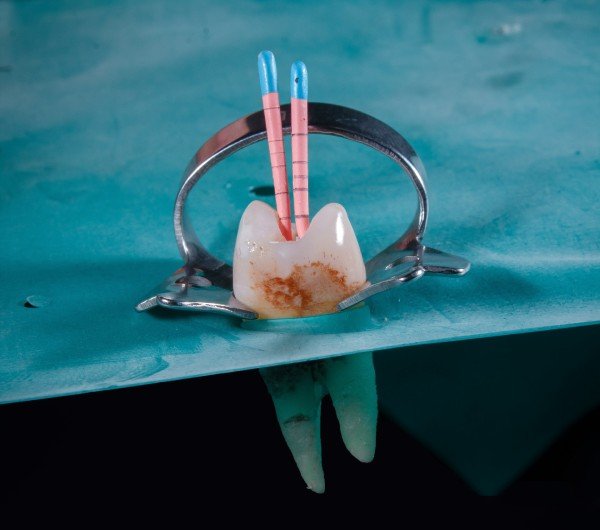

Root Canal Treatment

Root canal treatment, or endodontic therapy, involves removing infected or damaged tissue from inside a tooth, cleaning and shaping the root canals, and sealing them to prevent further infection. This procedure aims to save the tooth and alleviate pain caused by infection.